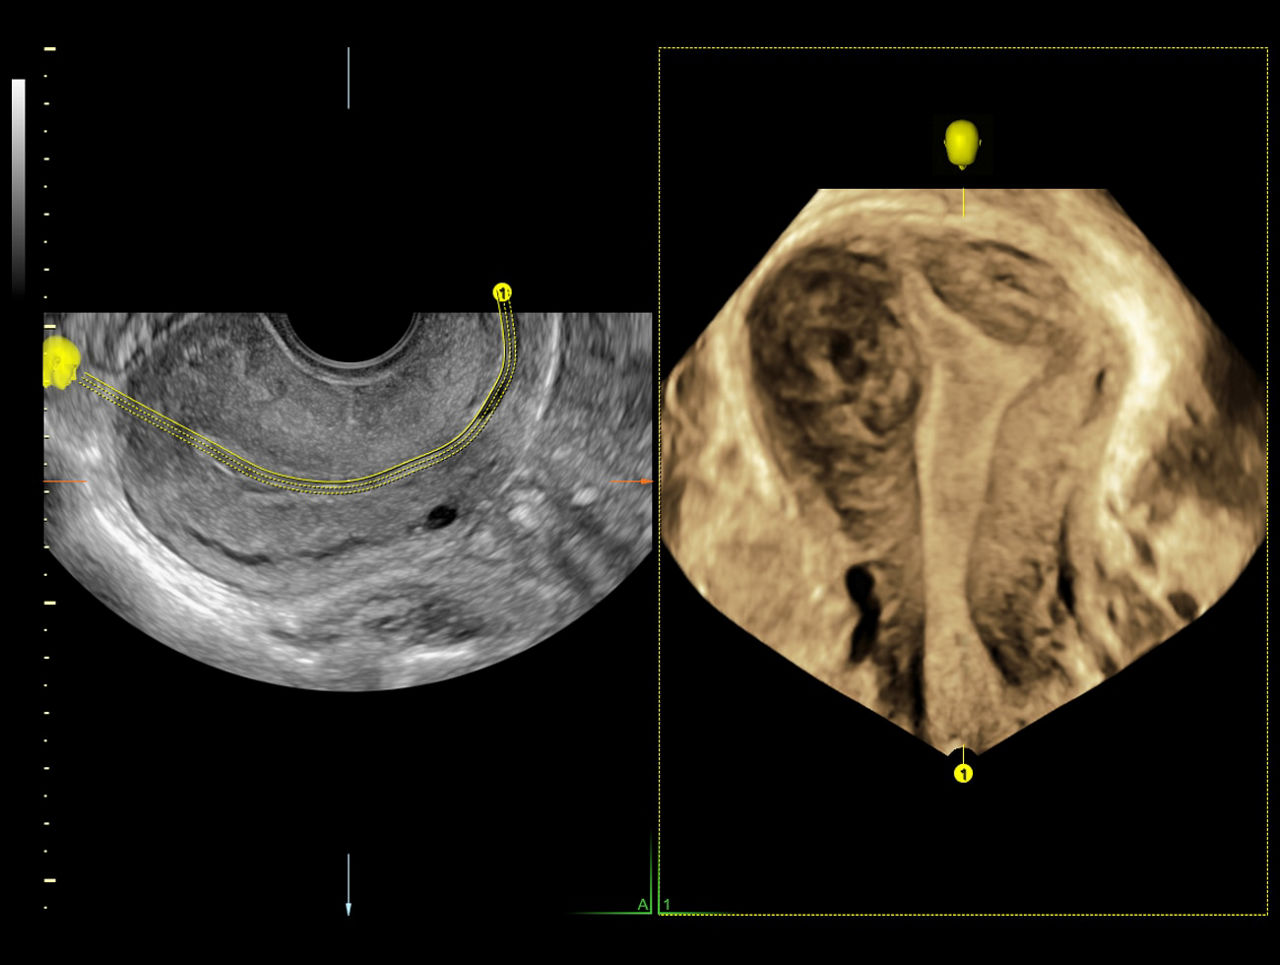

Uterine Trace

Incorporating 3D into your practice is easier than ever with Uterine Trace. From a standard view, simply trace the endometrium and the system automatically acquires a volume and then exacts the critical coronal view.